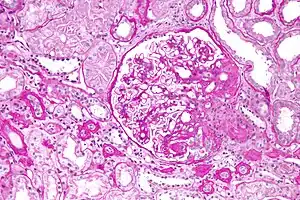

| Light micrograph of focal segmental glomerulosclerosis, hilar variant. Kidney biopsy. PAS stain. | |

The individual components of the name refer to the appearance of the kidney tissue on biopsy: focal—only some of the glomeruli are involved (as opposed to diffuse), segmental—only part of each glomerulus is involved (as opposed to global),[19] glomerulosclerosis—refers to scarring of the glomerulus (a part of the nephron (the functional unit of the kidney)). The glomerulosclerosis is usually indicated by heavy PAS staining and findings of immunoglobulin M (IgM) and C3-convertase (C3) in the sclerotic segment.[20]